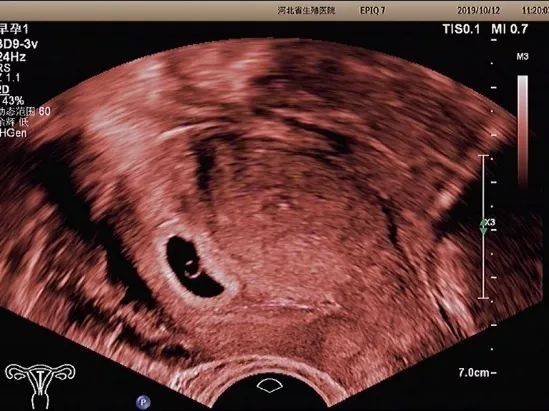

妊娠囊

肯定妊娠囊是否在宫腔内,妊娠囊在宫腔内的位置、数目及大小。妊娠囊的大小可随孕周增长而增长。

卵黄囊

卵黄囊是妊娠囊内超声能发现的第一个解剖结构。当超声发现卵黄囊,即可以肯定妊娠。正常的卵黄囊直径约3~8mm,卵黄囊过大、过小或不显示及变形均提示妊娠结局不良。

胚芽

可根据胚芽长度评估孕周,有无心管搏动,肯定胚胎是否存活。